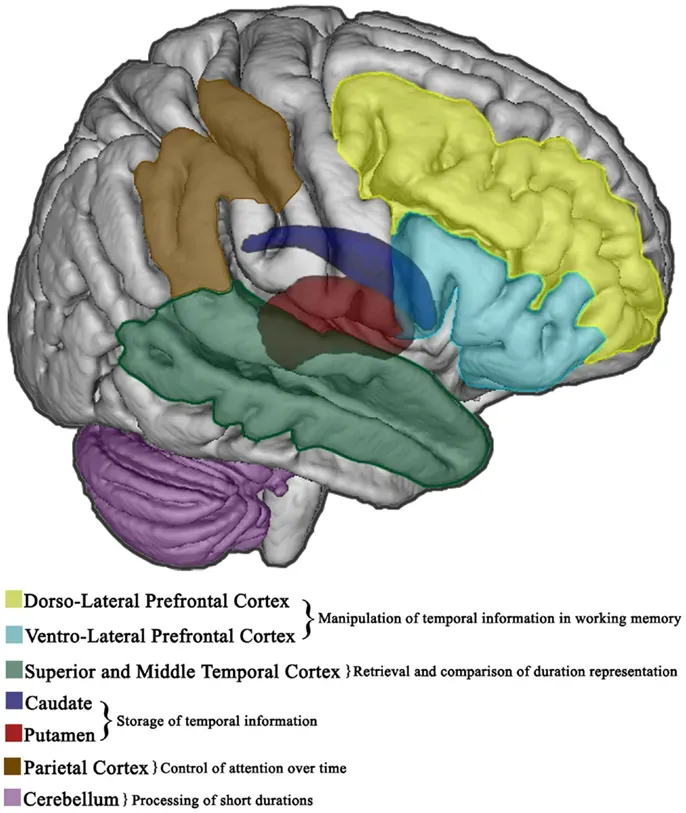

Timing Errors, Neural Echoes, and Pattern Tricks

One of the most compelling ideas about deja vu is that it can stem from tiny timing errors in how the brain processes incoming information. Picture two data streams arriving at a processor a fraction of a second apart; the second can seem like a repeat of the first, even though they are almost simultaneous. Some neurologists propose that similar desynchronization can occur between parallel pathways carrying perceptual input into memory systems. If one pathway delivers its signal slightly earlier, the later one may be tagged as “seen before,” even though both are part of the same continuous moment. In this view, deja vu is not a deep metaphysical message but an artifact of the brain’s split-second logistics.

Another line of research focuses less on timing and more on pattern recognition. The brain is constantly scanning the environment for familiar configurations, like the arrangement of a room or the rhythm of a conversation. When a new situation matches the underlying structure of a past one, even if the surface details are different, a surge of familiarity can arise without conscious access to the original context. That structural overlap can be enough to trigger the emotional tag of “already seen,” while leaving us scrambling to explain why. Deja vu, in that sense, is the subjective experience of the brain’s powerful but sometimes overenthusiastic pattern-matching systems.